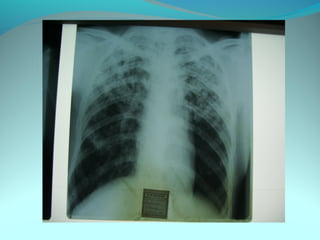

Image radiologique bilatirale a type d’opacité nodulaire occupant les

2/3 sup du poumon droit et la ½ sup du P G confluante par pour

former de grosses opacités

DIAGNOSTIC:

Tuberculose pulmonaire bilateral

Pneumonie bilaterale